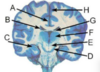

Label 5, 6 & 7

1 - superior temporal gyrus; 2 - inferior frontal gyrus; 3 - insular cortex; 4 - temporal stem; **5 - internal capsule;** **6 - thalamus;** **7 - lentiform nucleus** (the internal and external globus pallidus and the putamen) 8 - frontal horn; 9 - superior circular sulcus; 10 - inferior circular sulcus.